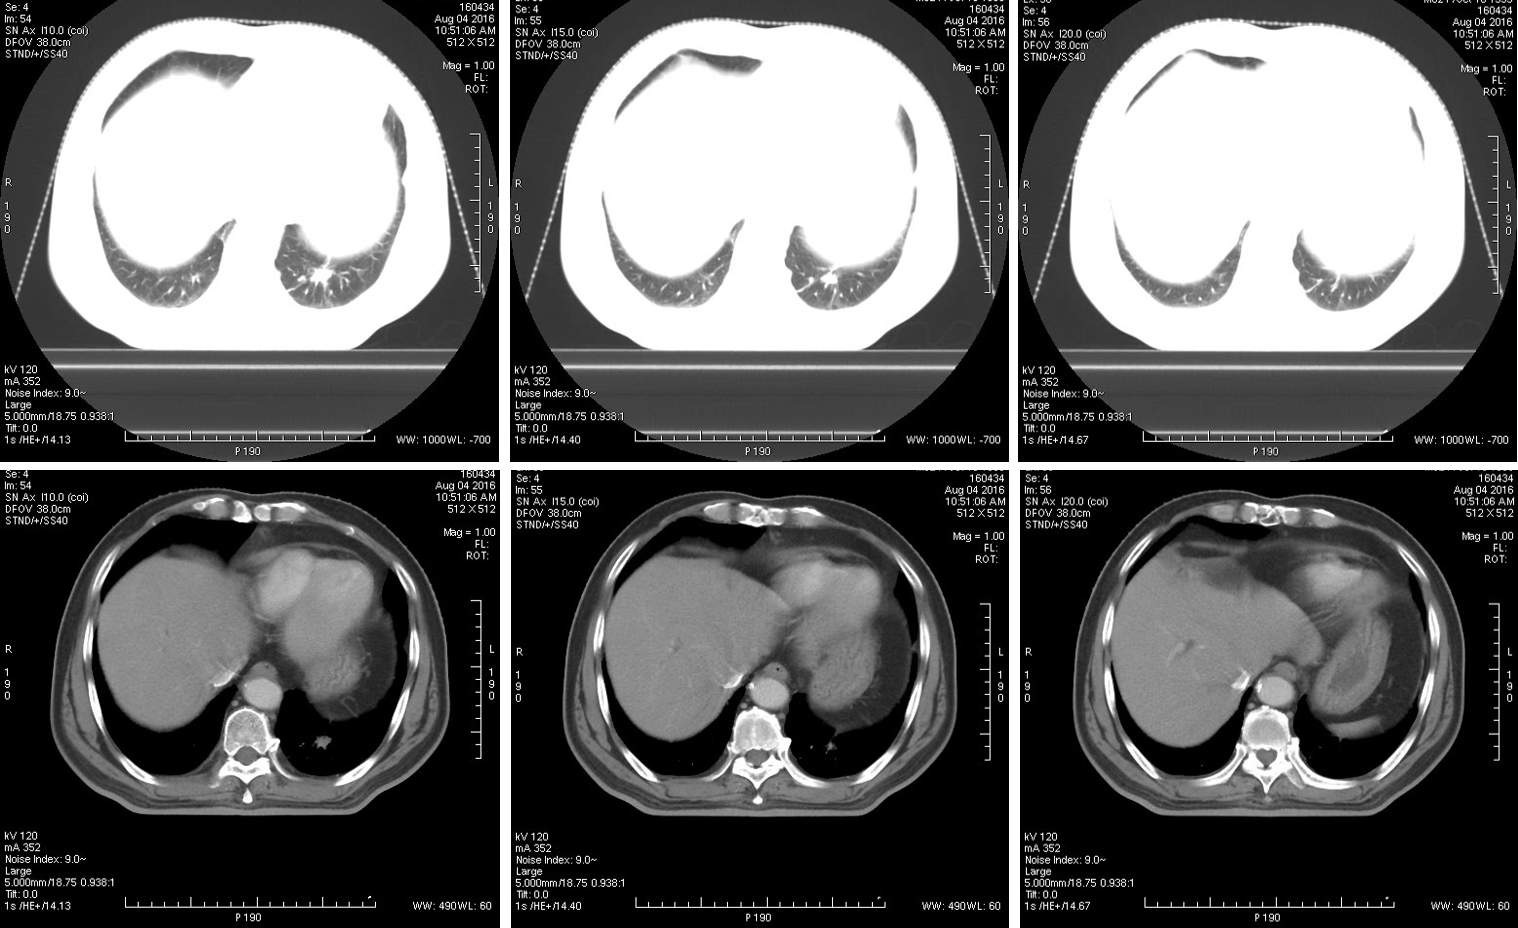

病例资料:男性,62岁,左下肺转移肿瘤。 扫描方法: 常规CT平扫

临床价值:使用4D-CT扫描可以准确评价肿瘤运动范围,确定肿瘤ITV(内靶区)。

在肿瘤最大层面测量,最大径为15.2mm。 4D呼吸门控扫描:

使用D4D呼吸门控扫描,可清楚观察到肿瘤本身随呼吸周期运动的情况。

使用A4D软件测量,肿瘤随呼吸周期的运动幅度近24mm。

扫描结束之后,使用Advantage 4D软件可把图像分成10个呼吸期相,生成MIP图、AveIP图和minIP图。使用Advantage SIM MD软件可以在4D运动的图像上实时勾画和修改靶区,确定肿瘤ITV,比过去凭经验外扩范围的方式,可更精确的确定肿瘤放射治疗的范围。此外,在Advantage SIM MD上勾画的靶区文件为RT DICOM格式,可以发送给TPS(放疗计划系统),TPS不仅可以读取,如有需要还可进行编辑。